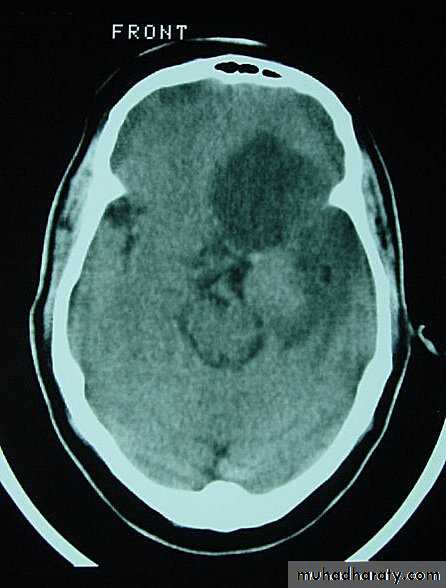

Metastatic Brain Tumours Pre contrast CT

• On CT, they only show well with intravenous contrast.